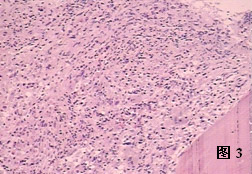

骨硬化病大多數患者在出生前即已開始有病變,根據臨床表現分惡性(幼兒型)及良性(成人型)。病因可能為先天性發育異常,有遺傳性及家族史.為常染色體顯性及隱性遺傳性疾病。病理表現為骨發育過程中骨吸收障礙,鈣鹽大量沉積致骨硬化。骨塑形障礙。最多見骨幹骺端即股骨及橈骨下端,肱骨及脛骨上端,鏡下見高度鈣化的軟骨不能吸收和骨化。鈣化的新生骨也不能吸收為成熟的板層骨,骨皮質分化不良,排列不整齊,哈佛氏系統殘缺變形。破骨細胞發育不全是骨吸收障礙的直接原因。但骨脆性增加易發生骨折。

骨硬化病病理改變

細胞圖臨床表現